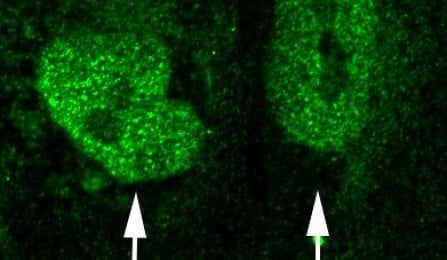

The researchers tested their hypothesis by creating an FGFR1 mutation in mice, which produced the hallmarks of the human disease: altered brain anatomy, behavioral impacts and overloaded sensory processes.

Image Source: The image shown is adapted from the University at Buffalo press release image.